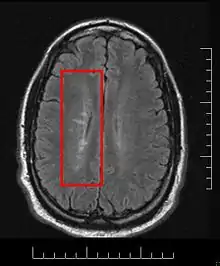

MS lesions

Normally MS lesions are small ovoid lesions, less than 2 cm. long, oriented perpendicular to the long axis of the brain's ventricles [18] Often they are disposed surrounding a vein[19]

Active and pre-active lesions appear as hyperintense areas under T2-weighted MRI. Pre-active lesion here refers to lesions localized in the normal appearing white matter, without apparent loss of myelin but nevertheless showing a variable degree of oedema, small clusters of microglial cells with enhanced major histocompatibility complex class II antigen, CD45 and CD68 antigen expression and a variable number of perivascular lymphocytes around small blood vessels[20]

This morphologic appearance was named Dawson's fingers by Charles Lumsden, after the Scottish pathologist James Walker Dawson,[31] who first defined the condition in 1916.

Dawson's fingers

"Dawson's fingers" is the name for the lesions around the ventricle-based brain veins[32][33] of patients with multiple sclerosis and antiMOG associated encephalomyelitis[34]

Though once thought to be specific of MS, it is known not to be the case.[35]

The condition is thought to be the result of inflammation or mechanical damage by blood pressure[30] around long axis of medular veins.

Dawson's fingers spread along, and from, large periventricular collecting veins, and are attributed to perivenular inflammation.[36]